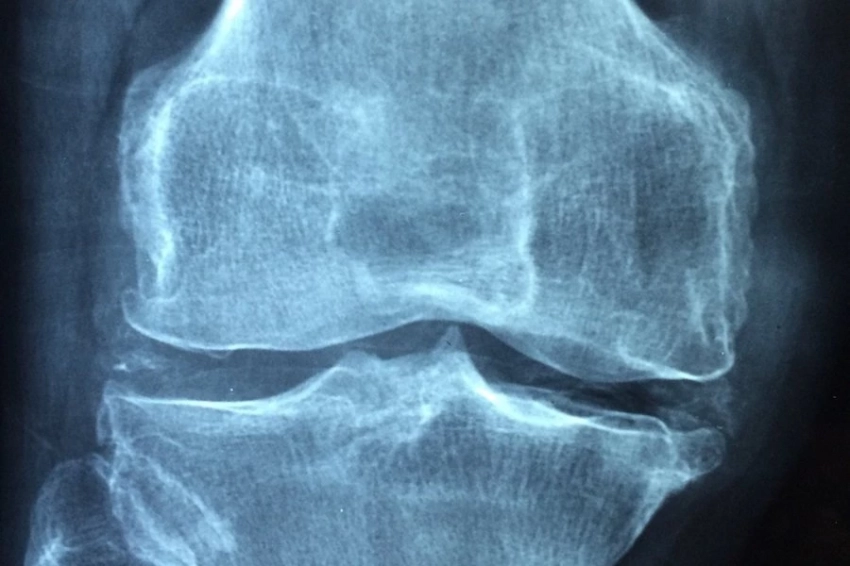

Учёные Karolinska Institutet (Швеция) обнаружили, что наличие старших братьев и сестер и удаление миндалин в детстве могут быть связаны с риском развития анкилозирующего спондилита (АС), характеризующегося воспалением суставов позвоночника, сообщается на портале BMJ.

Однако было обнаружено, что ампутация миндалин в детстве и наличие старших братьев или сестер могут быть связаны с увеличенным риском развития АС. Эти результаты были подтверждены как в случай-контрольном анализе, так и при сравнении данных братьев и сестер, что подчеркивает серьезность этих ассоциаций.